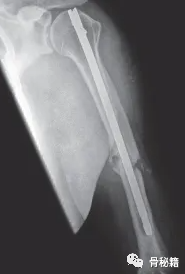

• 髓内钉:8-24个月 取出

断裂的内固定,需要更加充分的准备!

锁定螺钉难以取出时怎么处理?

3断的钉子怎么处理